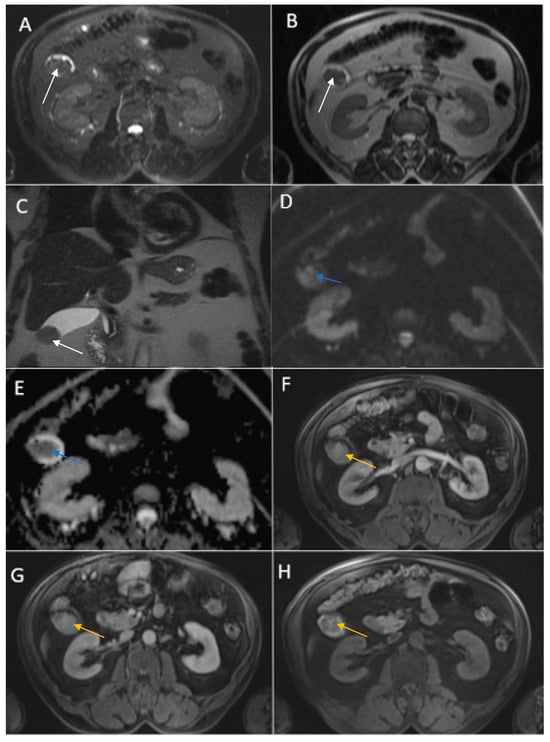

Figure 3. Abdominal MRI sequences highlighting imaging features suggestive of gallbladder carcinoma. (A) Diffusion-weighted imaging (DWI B800) showing bright high signal intensity of the wall thickening of the gallbladder (white arrow). (B) On apparent diffusion coefficient (ADC) map, the wall thickening is dark (black arrow)—illustrating markedly diffusion restriction—which in correlation with increased levels of CEA and CA 19-9 is highly suggestive of gallbladder carcinoma. (C) Axial T2-weighted FIESTA showing asymmetric strongly inhomogeneous wall thickening involving the gallbladder (yellow arrow). (DF). Axial contrast-enhanced T1-weighted images showing heterogeneous enhancement of the wall thickening (green arrows).

Therefore, clinical suspicion of gallbladder carcinoma was raised and an MRI cholangiography was performed (Figure 3). A laparoscopic cholecystectomy was performed and a subhepatic tumoral block with transvers colon invasion was identified. The patient was referred to the Oncology Department for further specialized treatment and follow-up.

Contrast-enhanced emergency CT (Figure 2) revealed mucosal hyperenhancement of the gallbladder, with irregular, mural thickening (16 mm), a gallstone (15 mm) and pericholecystic fluid and loco-regional inflammatory reactive lymph nodes (Panel A, Panel B and Panel C).

An acute cholecystitis complicated by pericholecystic abscess was diagnosed. The patient refused hospitalization and specialized treatment. The following day the patient returned to the Emergency Department with severe pain and was admitted directly to the General Surgery Department. Nevertheless, blood sample demonstrated increased levels of CEA (67.83 ng/mL) and CA 19-9 (110.20 U/mL), markers which brought to question the CT imaging diagnosis of an acute cholecystitis complicated by pericholecystic abscess.